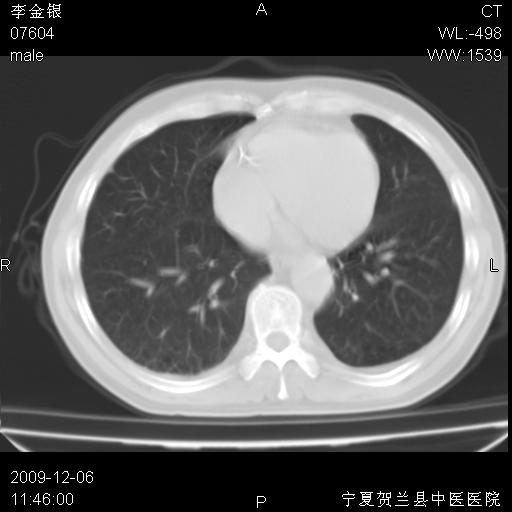

该病人 ,男,62岁,主因咳痰带血两天

考虑右肺中央型占位性病变并阻塞性肺炎.(右肺上叶支气管变窄),建议支纤镜检查.

支持右侧中央型肺癌伴上叶阻塞性炎症.

考虑右肺中心型肺癌伴阻塞性肺炎及右肺门淋巴结转移,建议纤维支气管镜进一步检查。

支气管壁明显增厚 管腔狭窄,腔静脉后多个淋巴肿大,结合年龄病史考虑右肺上叶中央型肺癌并阻塞性肺炎

右肺上叶后段支气管阻塞,右上肺门占位,相应肺段阻塞性肺炎,右肺门有淋巴结肿大。诊断右肺上叶中心型肺癌,阻塞性肺肺炎、右肺门淋巴结转移。

右上叶支气管狭窄,管壁增厚,远端斑片状软组织影,病灶邻近叶间裂,叶间裂无移位。

诊断右肺中央型肺癌。

那个片影应该大部分都是病灶,病灶沿肺段支气管分支生长,后段完全显示不清、闭塞。若为不张应该伴有叶裂的移位,若为炎症应有空气支气管征。